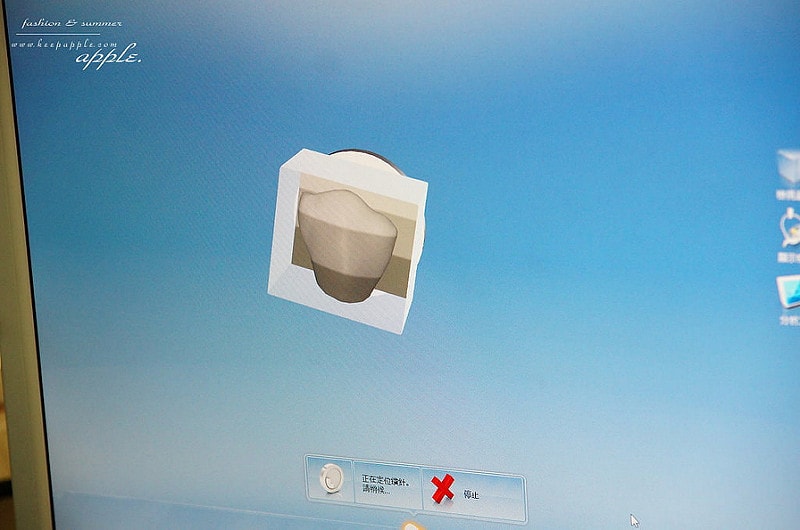

這顆就是要裝牙套的牙齒

會先像這樣磨成小小的

等一下好裝牙套

口掃完成之後

資料會傳輸到所有的資料會連動到

>>「3D全瓷冠4軸快速研磨機」上面

當場就可以把假牙研磨出來囉!

接下來就是等待就可以拉

像是掃描跟3D列印的道理一般